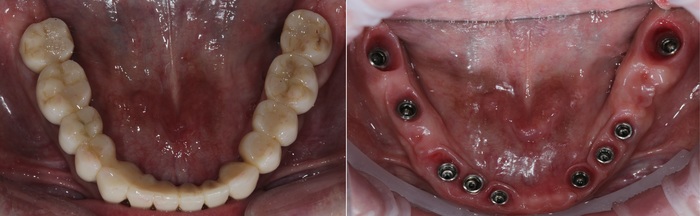

Далее проведена пластика десны, снова два месяца ожиданий и установка временной коронки:

Ну, такое, согласен, но это начало.

Еще через пару месяцев временную коронку сняли для изготовления новой:

И вот картинка спустя полгода «ношения» новой временной коронки: